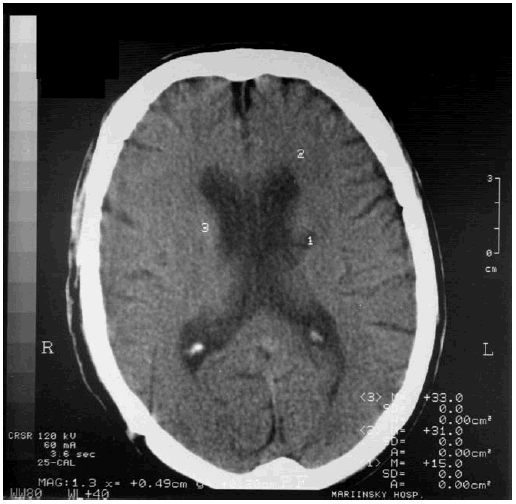

По нашим данным, полученным совместно с дерматовенерологом Л. Ф. Угрюмовой, в последние годы наблюдается рост менинговаскулярных форм нейросифилиса, ассоциированных с выраженными когнитивными расстройствами. В настоящее время не только в нашей стране, но и за рубежом отмечается нередко малосимптомный дебют нейросифилиса в виде единичных эпилептических приступов, хронической головной боли, изолированной атрофии зрительных нервов, корковой атаксии, с постепенным развитием когнитивных расстройств. В этих случаях результаты КТ головного мозга зачастую не выявляют патологических изменений или обнаруживается картина умеренной гидроцефалии и церебральной атрофии. На рис. 9.3 представлена КТ головного мозга пациента с нейросифилисом и умеренной деменцией, выявляется выраженная внутренняя гидроцефалия.

Рис. 9.3. КТ головного мозга у пациента с нейросифилисом и деменцией